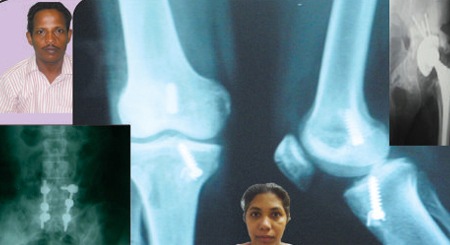

Italy - TKR